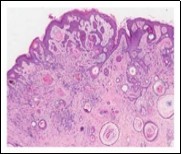

Lesions are generally superficial and infrequently invade lower dermis. Tendency for peri-neural or intra-neural infiltration, cogitated in adjunctive cutaneous carcinomas, is exceptional in desmoplastic trichoepithelioma. Nevertheless, desmoplastic trichoepithelioma can be exemplified as a component of particularly desmoplastic, cutaneous carcinomas demonstrating foci of peri-neural involvement 4, 5. Figure 1, Figure 2, Figure 3, Figure 4, Figure 5, Figure 6, Figure 7, Figure 8.

Figure 3.Desmoplastic trichoepithelioma exhibiting accumulated basaloid epithelial cells disseminated amongst a background of abundant fibrous tissue stroma and an attenuated superimposed epidermis 10.